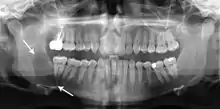

التورم هو العرض الأكثر شيوعا , لكن يمكن لأورام الأكياس الكيراتينية سنية المنشأ أن تكون بدون أعراض مرضية و أن يتم اكتشافها صدفة على صور الأشعة السنية للأسنان .[4]

التشخيص التفريقي بالأشعة